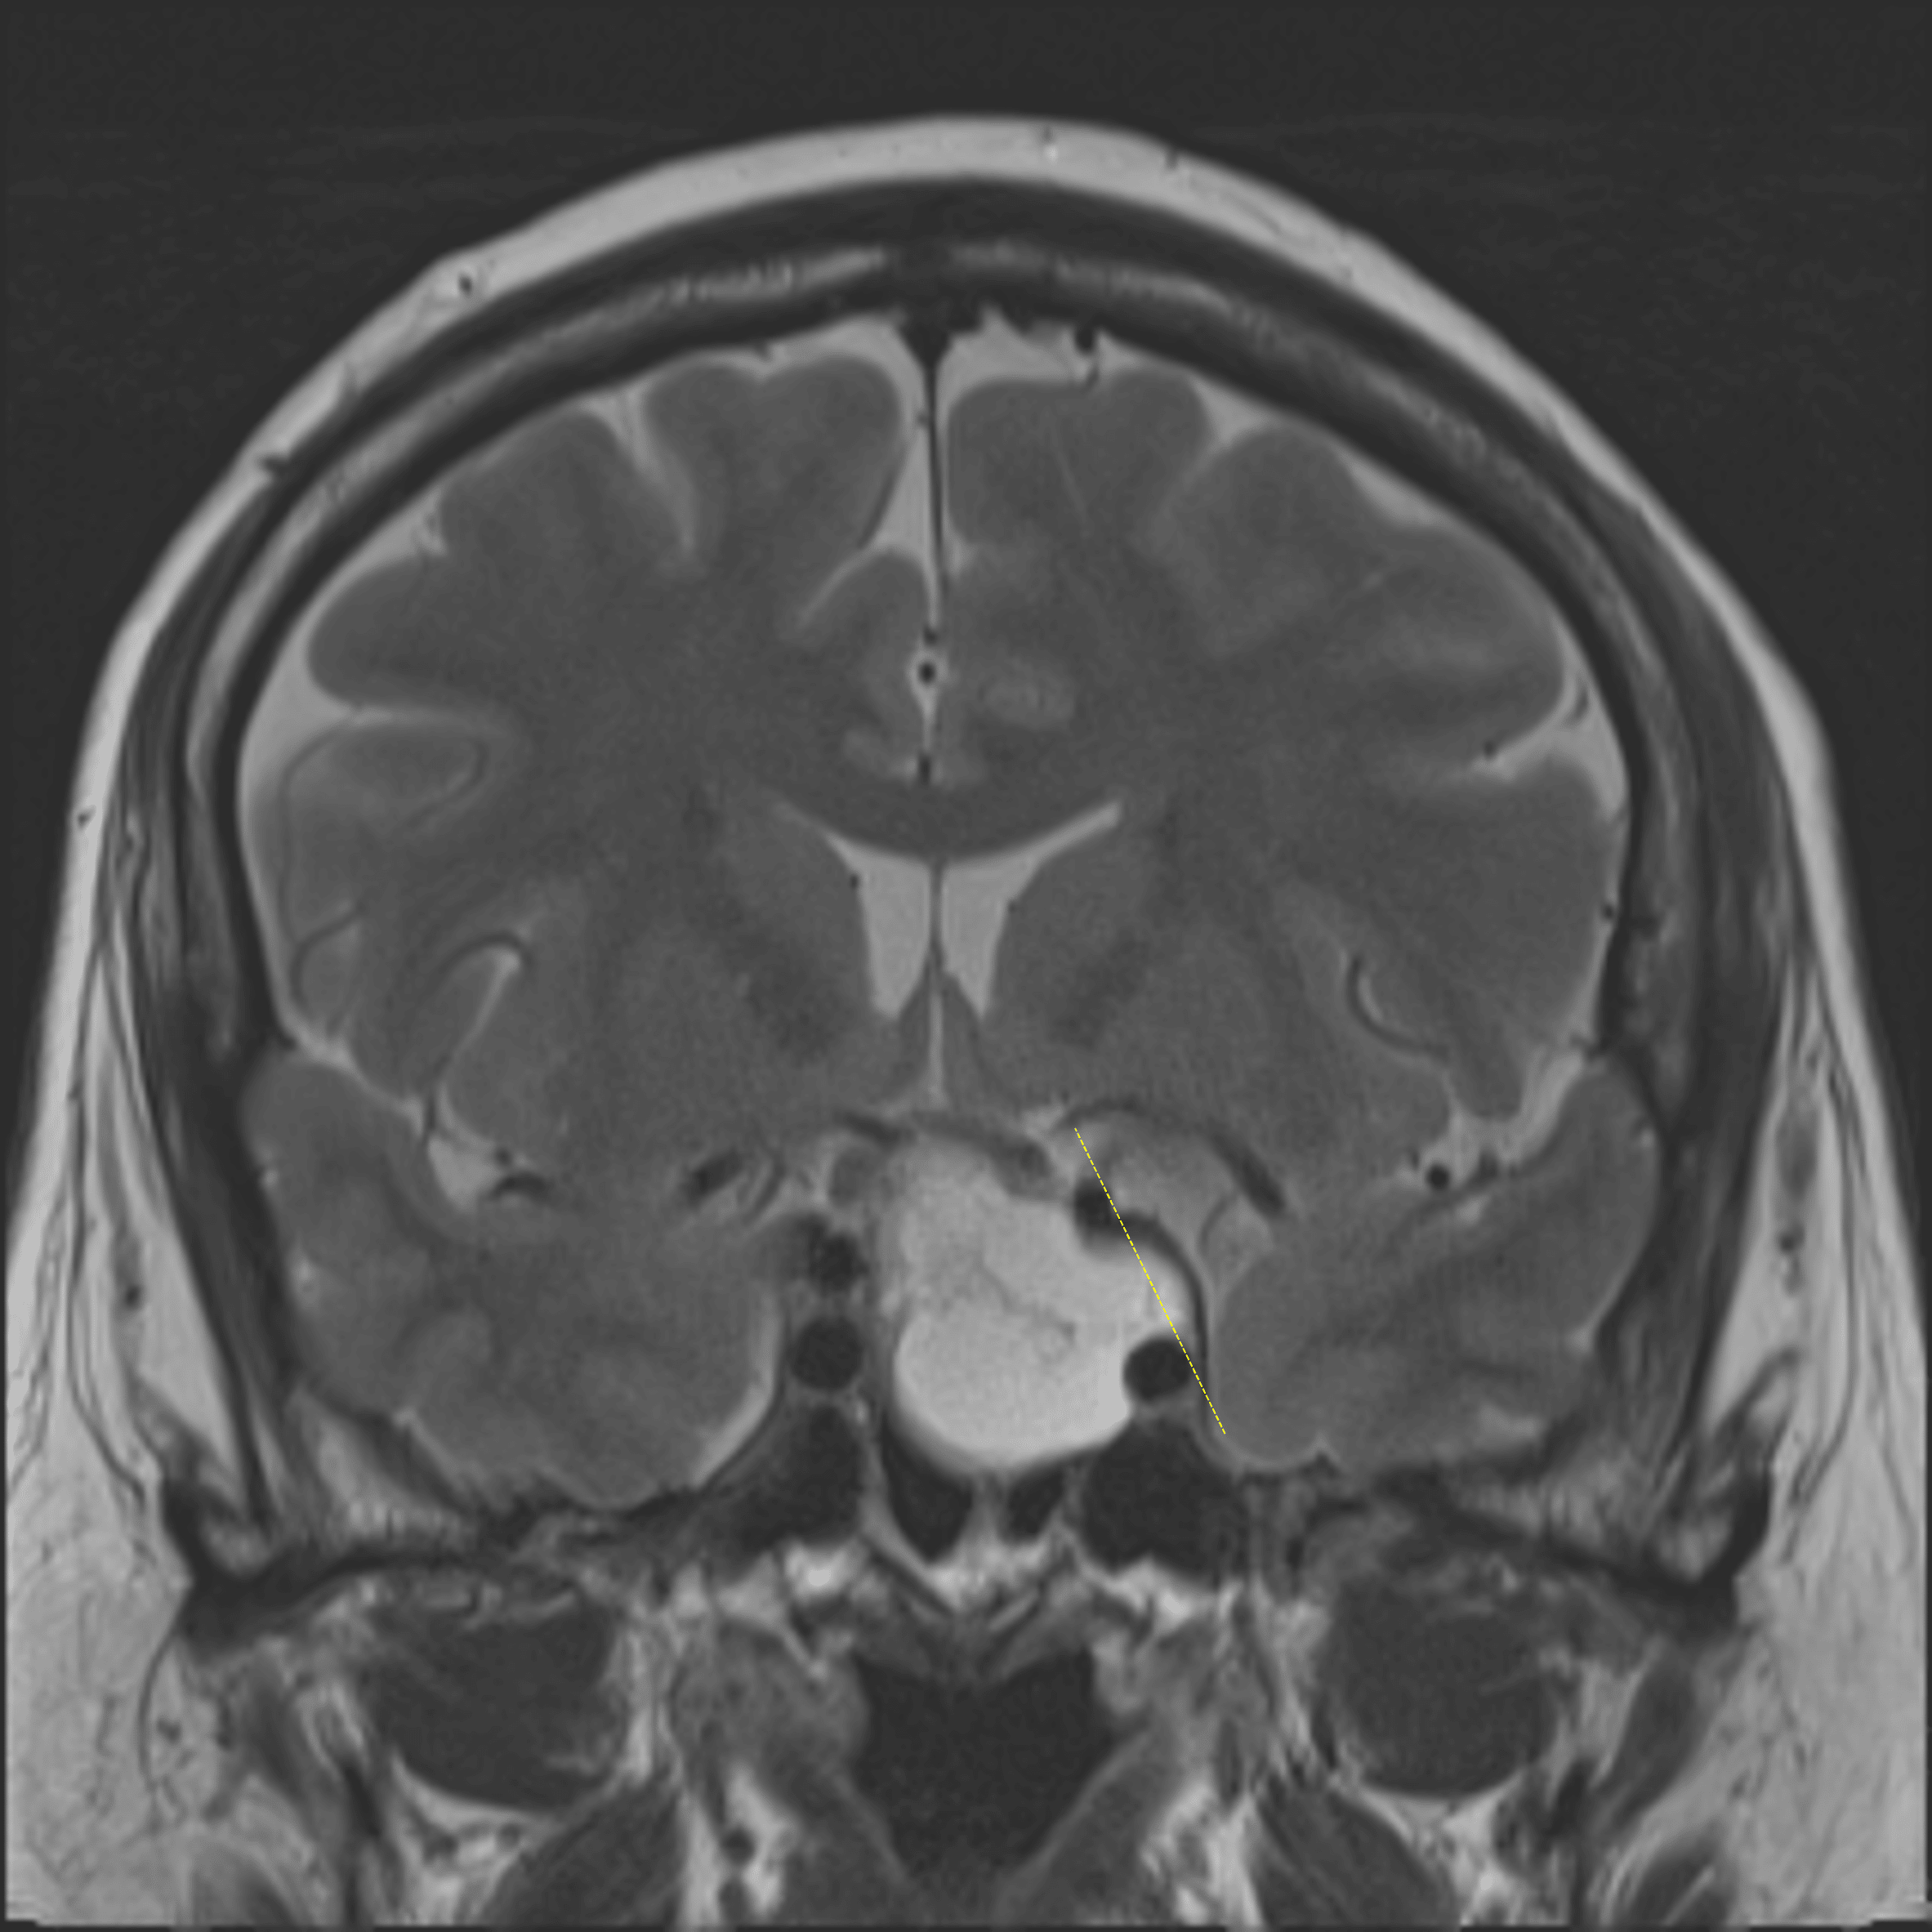

Tumor bulges lateral to the left lateral carotid tangent line (yellow dotted line), suggesting cavernous sinus invasion.

Cystic pituitary macroadenoma